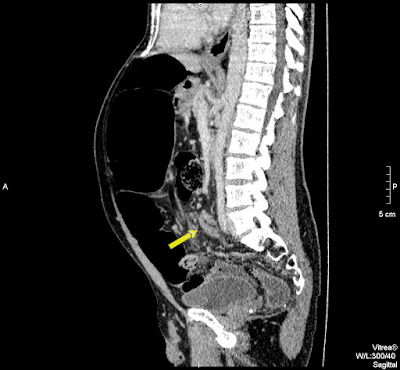

45 koruli ferfi. Elozmenyben hasi mutet nincsen. Ket napja puffad a beteg hasa, azota nincsen szeklet. A CRP minimalisan emelkedett, a FVS normalis. Laz nincsen, feszes, gazos has.

A zsirdenzitas a mesenterium „beforgasat” jelzi a belfal negyezte koze az organo-axialis formanak megfeleloen.

Azert nincs szep whirlpool sign = signe de tourbillone = orveny jel?, mert nem a mesenterium a forgastengely, hanem maga a sigma.